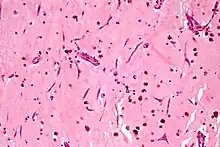

Atrial myxoma. H&E stain.

Atrial myxoma. H&E stain. -